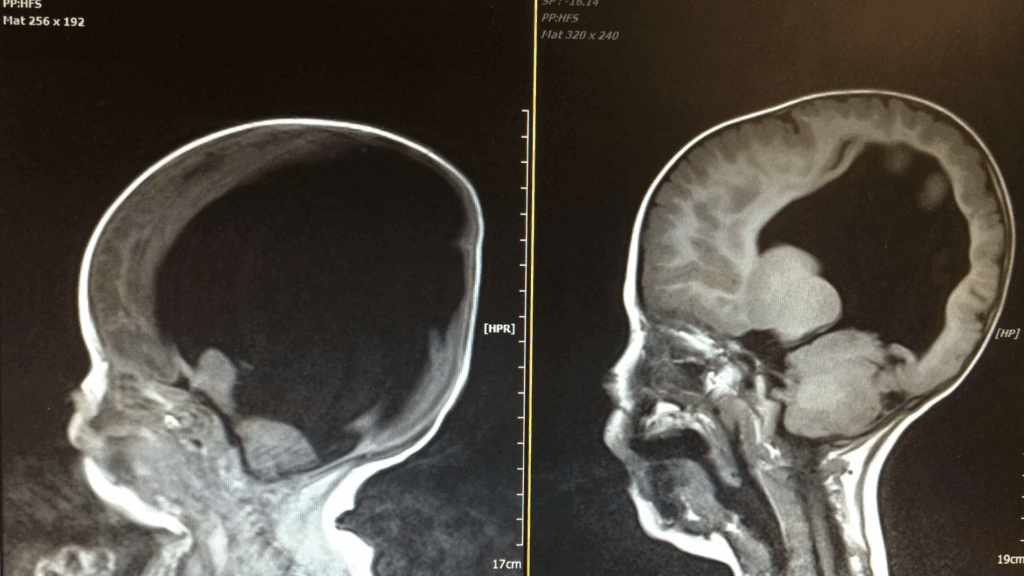

The Shocking MRI Results

An MRI scan shortly after birth revealed stunning news. Noah was actually born with just two percent of his physical brain. This was far worse than doctors had anticipated. A thin layer of brain tissue existed only at the front of his head. The porencephalic cyst had destroyed most of his developing brain. Medical staff prepared his parents for a vegetative state existence.

Within three years, Noah’s brain remarkably grew from two percent to 80 percent. Scientists believe his brain tissue was compressed rather than absent. The shunt allowed room for his brain to expand properly. Noah began responding to environmental cues in ways doctors couldn’t explain. He could see, hear, and communicate despite missing crucial brain regions. Medical professionals struggled to understand his incredible recovery.